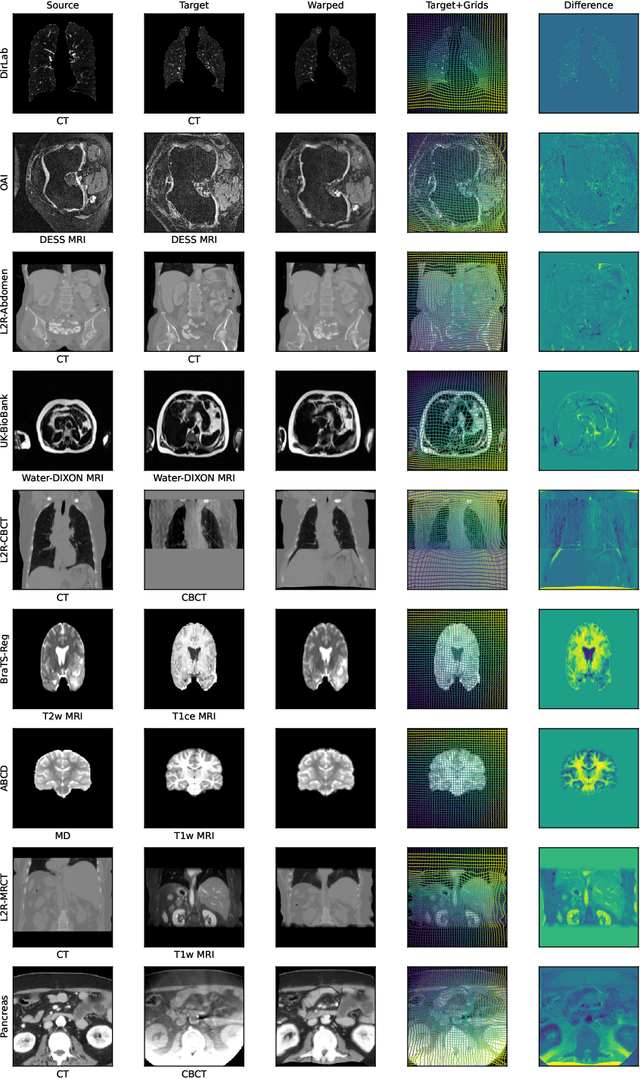

Abstract:Modern medical image registration approaches predict deformations using deep networks. These approaches achieve state-of-the-art (SOTA) registration accuracy and are generally fast. However, deep learning (DL) approaches are, in contrast to conventional non-deep-learning-based approaches, anatomy-specific. Recently, a universal deep registration approach, uniGradICON, has been proposed. However, uniGradICON focuses on monomodal image registration. In this work, we therefore develop multiGradICON as a first step towards universal *multimodal* medical image registration. Specifically, we show that 1) we can train a DL registration model that is suitable for monomodal *and* multimodal registration; 2) loss function randomization can increase multimodal registration accuracy; and 3) training a model with multimodal data helps multimodal generalization. Our code and the multiGradICON model are available at https://github.com/uncbiag/uniGradICON.